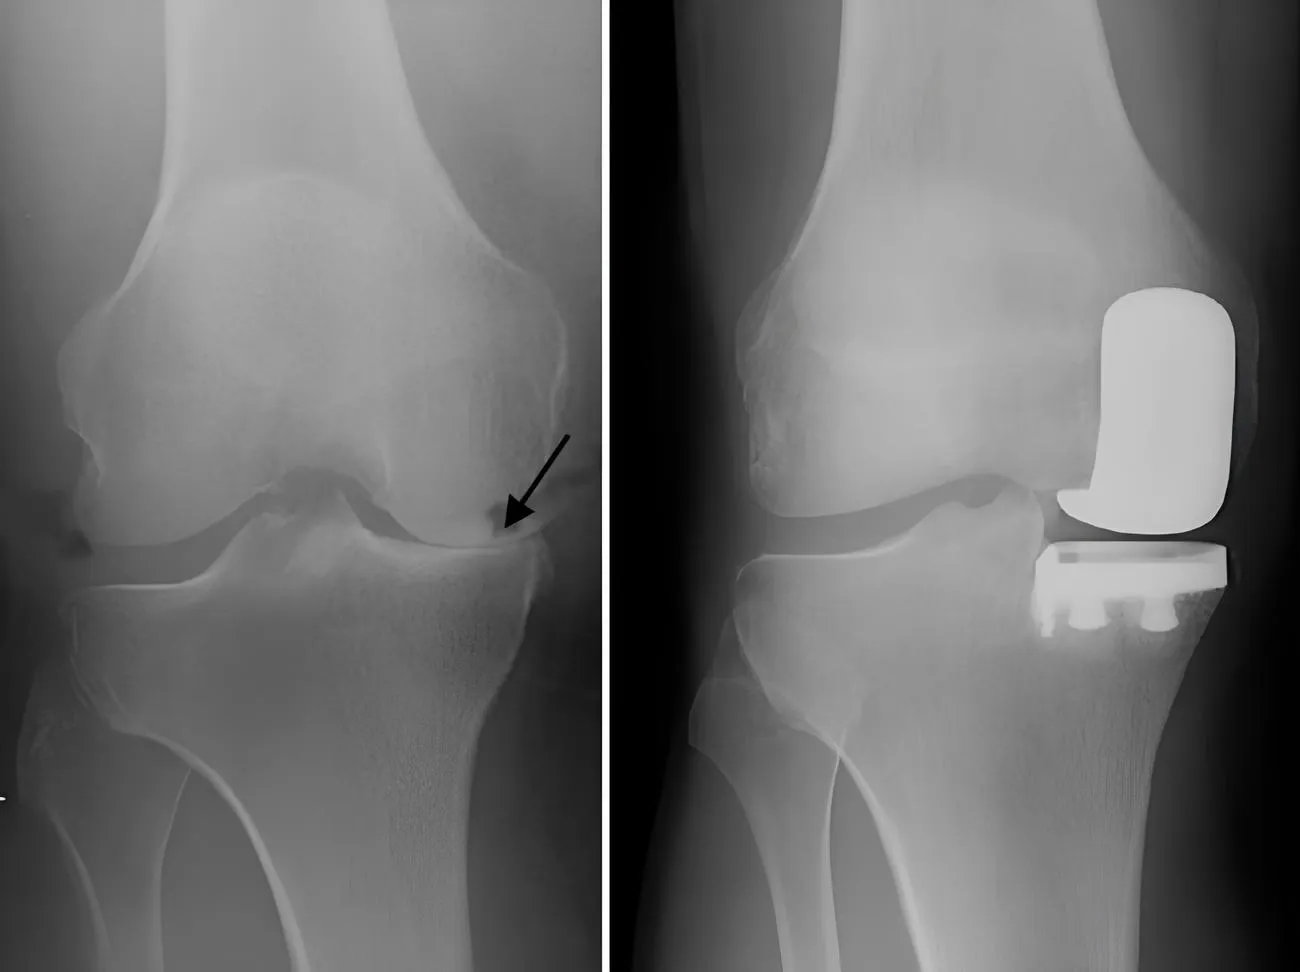

Partial Knee Replacement

Unicondylar knee replacement